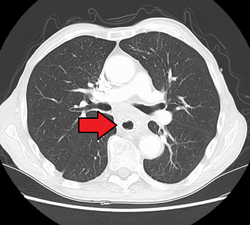

Additional testing is needed to assess how much the cancer has spread (see § Staging, below). Computed tomography (CT) of the chest, abdomen and pelvis can evaluate whether the cancer has spread to adjacent tissues or distant organs (especially liver and lymph nodes). The sensitivity of a CT scan is limited by its ability to detect masses (e.g. enlarged lymph nodes or involved organs) generally larger than 1 cm.[43][44] Positron emission tomography is also used to estimate the extent of the disease and is regarded as more precise than CT alone.[45] PET/MR as a novel modality has shown promising results in preoperative staging with fair feasibility and good correlation in comparison to PET/CT. It can enhance tissue differentiation with lowering the radiation dose to the patient.[46] Esophageal endoscopic ultrasound can provide staging information regarding the level of tumor invasion, and possible spread to regional lymph nodes.

Contrast CT scan showing an esophageal tumor (axial view)